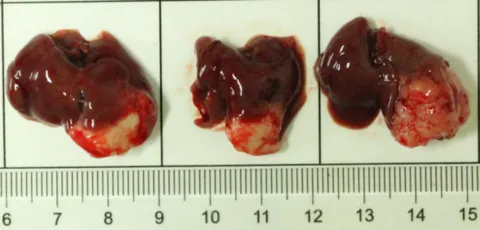

部分beats365PDX原位模型展示

部分beats365PDX原位模型展示